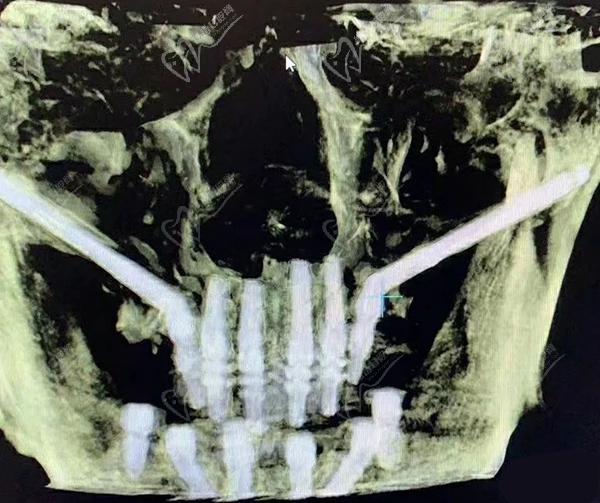

穿顴種植手術(shù),是通過將兩顆超長(zhǎng)植體斜植入顴骨來獲得超高的固位成效,然后在前牙區(qū)在垂直植入2-3顆普通植體,對(duì)于頜骨吸收情況比較重的牙友可以使用四顆穿顴種植體。穩(wěn)定性非常強(qiáng),是即刻種植修復(fù)技術(shù),大大縮短了種植牙時(shí)間,避免了大量植骨帶來的愈合等待期和風(fēng)險(xiǎn)。

在做穿顴種植手術(shù)的時(shí)候,因?yàn)橛袃深w植體斜插入顴骨貫穿面部神經(jīng)和血管區(qū),所以,需要在術(shù)前進(jìn)行詳細(xì)的CBCT頜面檢查,提取上頜竇等影響數(shù)據(jù)來確定非常精密的植入方案,來避免損傷神經(jīng)。大家做穿顴種植手術(shù)的時(shí)候切記要選擇正規(guī)醫(yī)院。

醫(yī)生要詳細(xì)了解術(shù)區(qū)的臨近動(dòng)脈、靜脈、神經(jīng),且植體長(zhǎng)度是常規(guī)植體的3-5倍長(zhǎng),起端極小的角度偏差都會(huì)導(dǎo)致末端的巨大偏離,造成手術(shù)失敗或損傷神經(jīng)的風(fēng)險(xiǎn),手術(shù)精細(xì)度非常高。

穿顴種植手術(shù)一般為上牙列穿顴種植、下牙列all-on-4種植,全口種植流程需要2.5小時(shí)完成,實(shí)現(xiàn)一日得穿顴種植技術(shù)。術(shù)前進(jìn)行全口CT掃描、3D頭骨模擬重建等,精細(xì)確認(rèn)牙友骨量不足的程度、上頜竇底骨質(zhì)薄的數(shù)據(jù),確保手術(shù)更安心。